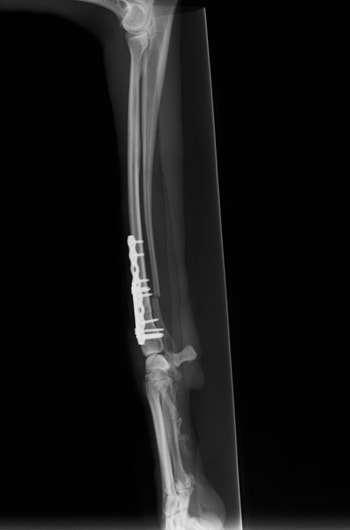

橈尺骨骨折 : 症例1 | 症例2 | 症例3 | 症例4 | 症例5 | 症例6 | 症例7

トイプードル 右遠位橈尺骨短斜骨折のALPSによる内固定

Locking Compression Plate

LCPは、スクリュー(ネジ)とプレート(金属の板)をロックする特殊な構造により骨折部位を固定する新しい世代のプレートシステムです。ひとつのホールでロッキングスクリューとスタンダードスクリューの使用を選択できるユニークな構造をしているため、骨折断端間の圧迫を目的とした従来型プレート固定法に加え、高い角度安定性を有するロッキングスクリューを用いた固定法の選択が可能です。従来のプレートシステムでは困難だった部分の骨折や癒合不全の症例に高い治療効果をもたらします。